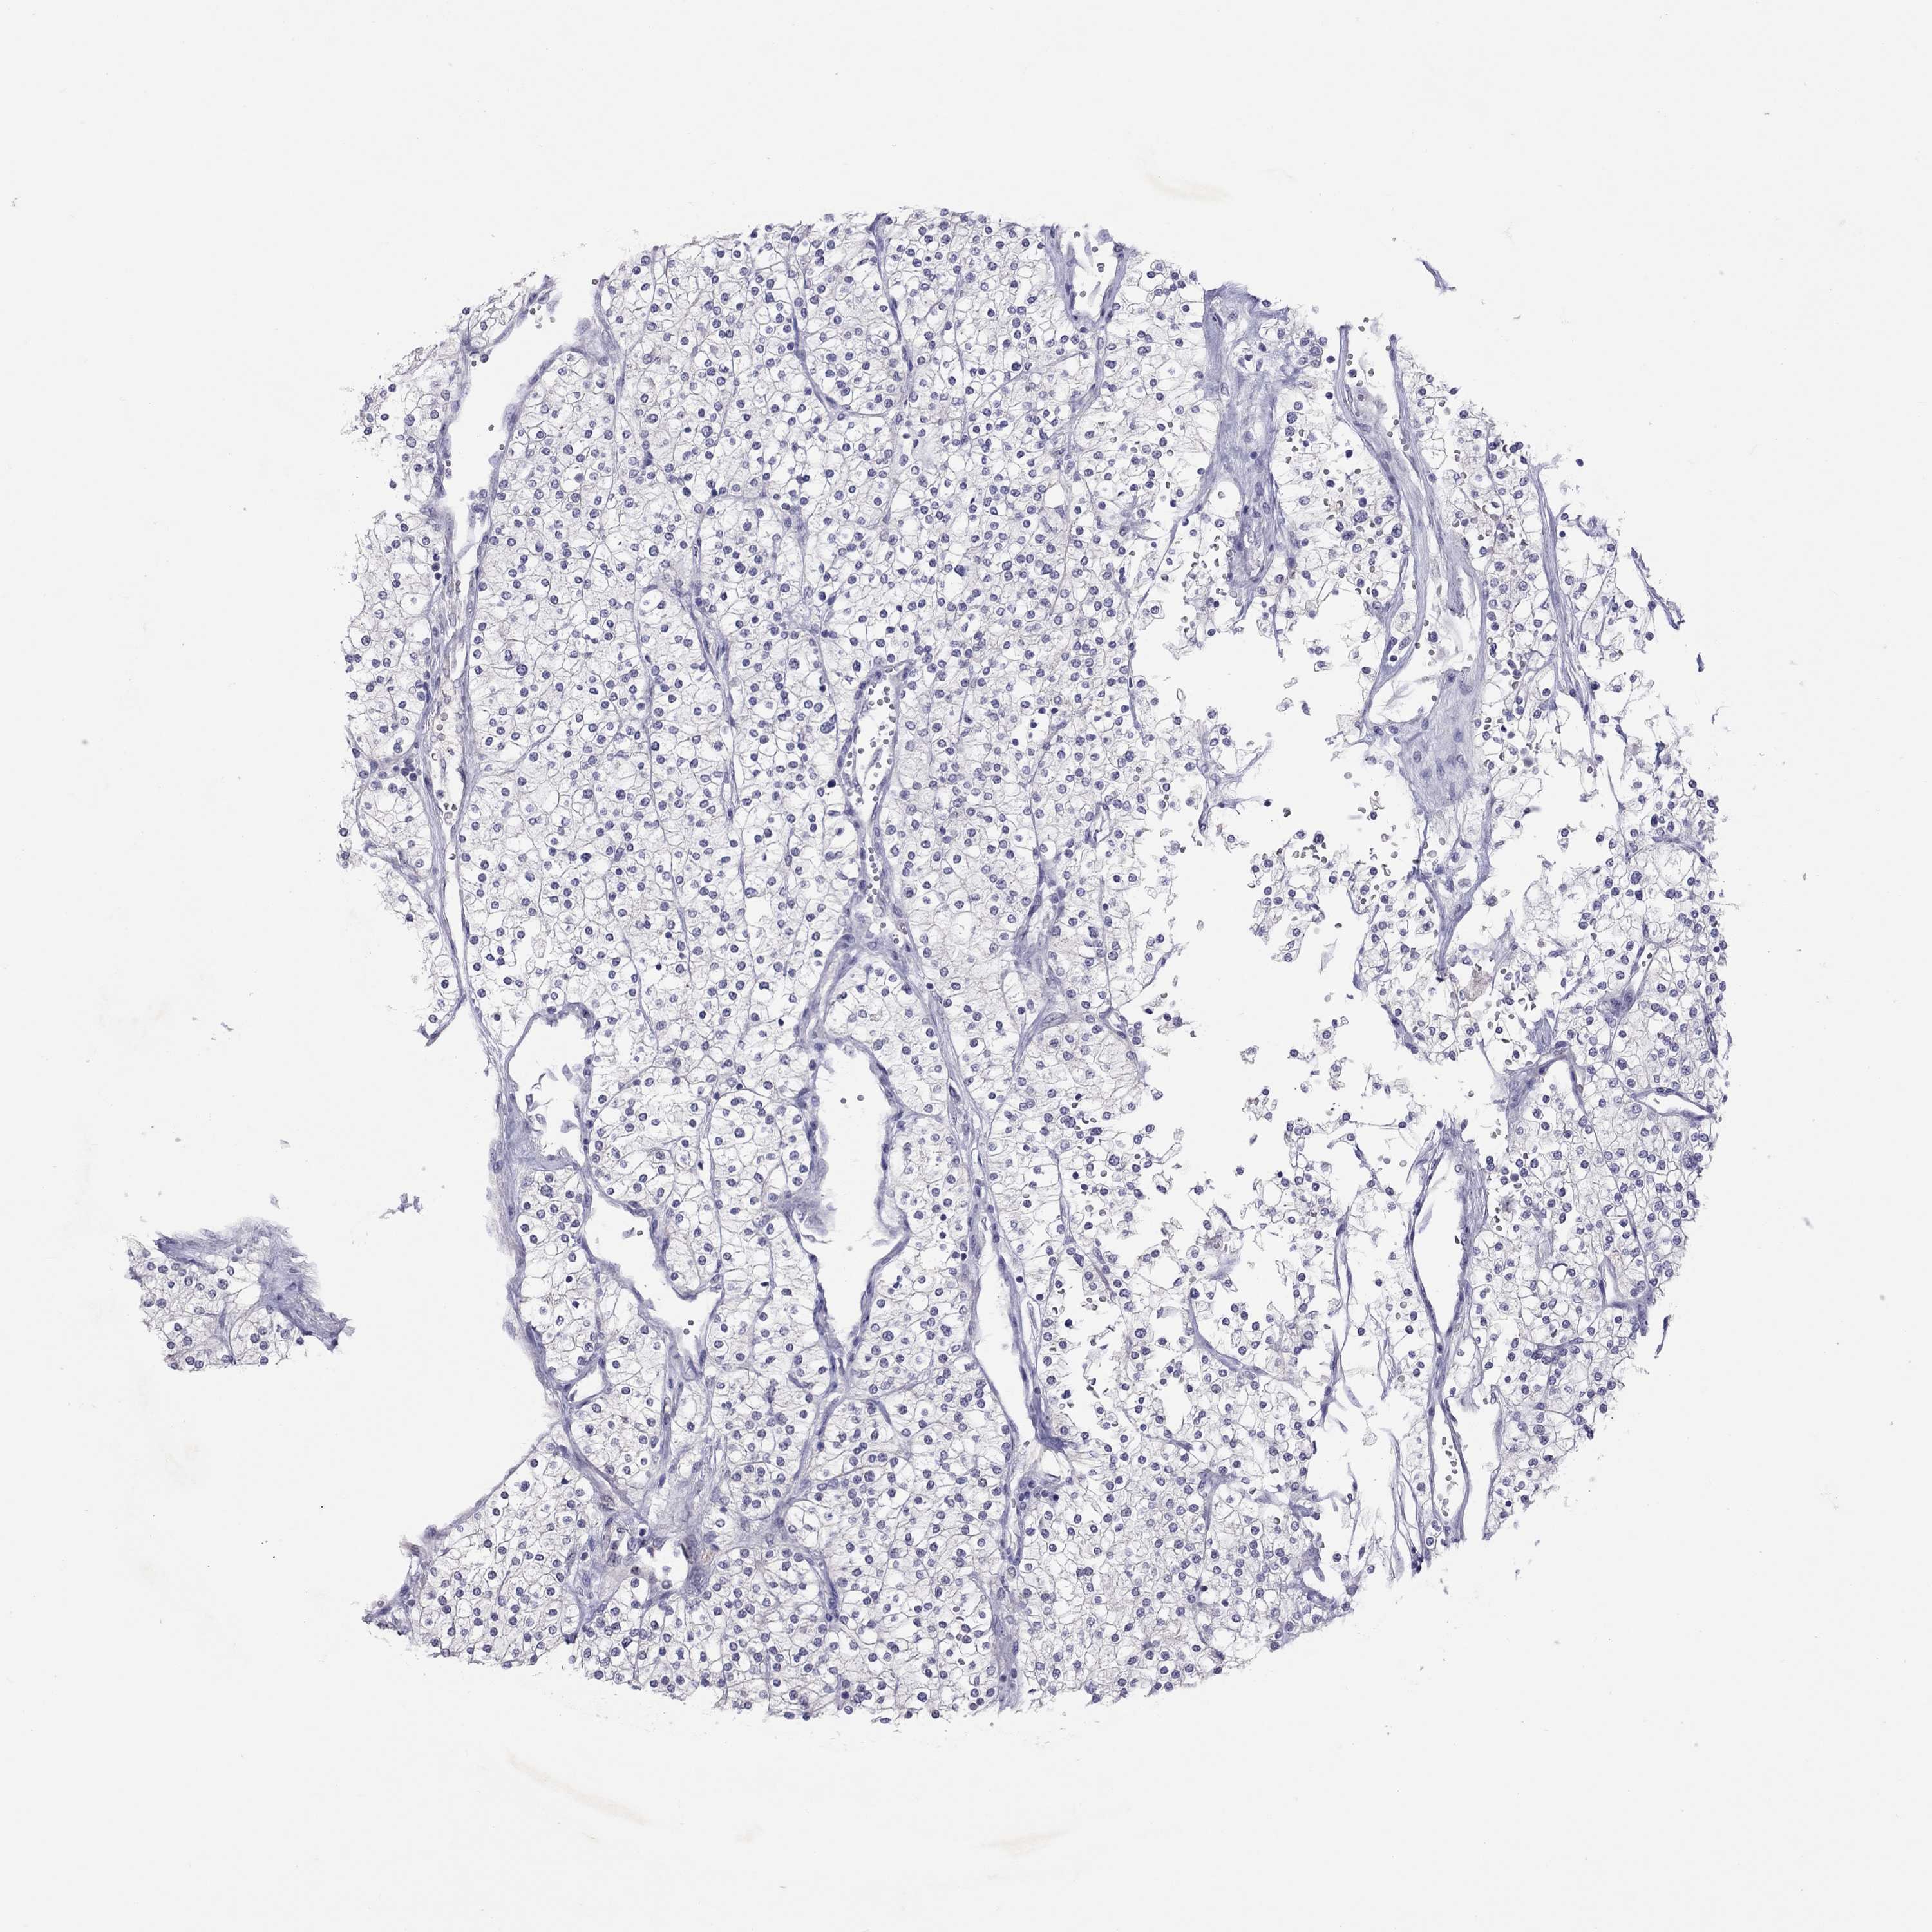

KIDNEY RENAL CLEAR CELL CARCINOMA (VALIDATION) - Interactive survival scatter ploti

The Survival Scatter plot shows the clinical status (i.e. dead or alive) for all individuals in the patient cohort, based on the same data that underlies the corresponding Kaplan-Meier plots. Patients that are alive at last time for follow-up are shown in blue and patients who have died during the study are shown in red.

The x-axis shows the expression levels (FPKM) of the investigated gene in the tumor tissue at the time of diagnosis. The y-axis shows the follow-up time after diagnosis (years). Both axes are complimented with kernel density curves demonstrating the data density over the axes. The top density plot shows the expression levels (FPKM) distribution among dead (red) and alive patients (blue). The right density plot shows the data density of the survived years of dead patients with high and low expression levels respectively, stratified using the cutoff indicated by the vertical dashed line through the Survival Scatter plot. This cutoff is automatically defined based on the FPKM cutoff that minimizes the p-score. The cutoff can be changed by dragging the vertical line or by entering a cutoff value in the square labeled "Current cut-off".

Under the Survival Scatter plot the p-score landscape (black curve; left axis) is shown together with dead median separation (red curve; right axis). Dead median separation is the difference in median mRNA expression between patients who have died with high and low expression, respectively. It is calculated as follows: median FPKM expression of dead patients with high expression - median FPKM expression of dead patients with low expression. This is intended to aid the user in visually exploring custom cutoffs and the associated p-scores and dead median separation.

Individual patient data is displayed and can be filtered by clicking on one or more of the category buttons on the top of the page. Categories describing expression level and patient information include: high, low, alive, dead, female, male and tumor stages. The scale of the x-axis can be toggled between linear and log-scale by clicking on the "x log" button. Mouse-over function shows TCGA ID, patient information and mRNA expression (FPKM) for each patient.

& Survival analysisi

Kaplan-Meier plots summarize results from analysis of correlation between mRNA expression level and patient survival. Patients were divided based on level of expression into one of the two groups "low" (under cut off) or "high" (over cut off). X-axis shows time for survival (years) and y-axis shows the probability of survival, where 1.0 corresponds to 100 percent.

JHY is not prognostic in Kidney Renal Clear Cell Carcinoma (validation)

Best expression cut offi

Based on the FPKM value of each gene, patients were classified into two groups and association between prognosis (survival) and gene expression (FPKM) was examined. The best expression cut-off refers the FPKM value that yields maximal difference with regard to survival between the two groups at the lowest log-rank P-value. Best expression cut-off was selected based on survival analysis .

When clicking on this number, the vertical dashed line indicating cut-off, the interactive survival plot, and the Kaplan-Meier curve will be adjusted to show results based on the best expression cut-off.

: 6.06

Median expressioni

Median expression refers to the median FPKM value calculated based on the gene expression (FPKM) data from all patients in this dataset. When clicking on this number, the vertical dashed line indicating cut-off, the interactive survival plot, and the Kaplan-Meier curve will be adjusted to show results based on the median expression.

: N/A

Median follow up timei

Median follow up time refers to the median time (years) after diagnosis with this type of cancer, based on clinical data from all patients in this dataset.

P scorei

Log-rank P value for Kaplan-Meier plot showing results from analysis of correlation between mRNA expression level and patient survival.

N/A

5-year survival highi

5-year survival for patients with higher expression than the expression cutoff.

For melanoma and glioma, 3-year survival is shown.

5-year survival lowi

5-year survival for patients with lower expression than the expression cutoff.

TCGA RNA samplesi

RNA-seq data is reported as average FPKM (number Fragments Per Kilobase of exon per Million reads), generated by the The Cancer Genome Atlas (TCGA) .

Normal distribution across the dataset is visualized with box plots, shown as median and 25th and 75th percentiles. Points are displayed as outliers if they are above or below 1.5 times the interquartile range. FPKM values of the individual samples are presented next to the box plot.

Average pTPM 4.3

Number of samples 100